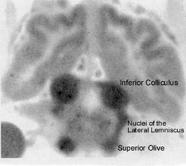

| Figure11 is a diagram of the auditory pathway from the cochlear nerve in the lower brainstem to the temporal lobes of the cerebral cortex. The inferior colliculi are the posterior pair of "hills" (Latin colliculi) in the midbrain tectum. Figure 12 is an autoradiogram from the investigations of Landau et al. (1955) on cerebral blood flow [1]; it shows the greatest uptake of radioactive tracer in the inferior colliculi. Figure 12 can be compared with figure 11 for location of the inferior colliculi, the superior olives, and the lateral lemniscal tracts connecting these important way stations in the brainstem auditory pathway. The dramatic autoradiographic picture in figure 5 is from a paper by Kety (1962), who was director of the group that first used radioactive tracers to study blood flow in the brain [2]. Figure 6 from observations of myelination by Yakovlev and Lecours (1967) shows that the greatest degree of myelin development in a human fetus at 29 weeks gestation is in the same structures with highest blood flow, the inferior colliculi and the lateral lemniscal tract connections to it from the superior olives [3]. Myelination is an important measure of maturation, and the study by Yakovlev and Lecours confirmed earlier research by Langworthy (1933) who also found the auditory system of the brain among the earliest to mature [4]. Langworthy's data is shown in figure 7. Confirmation of early myelination and function of the auditory system can be found in the paper by Moore et al. (1995) [5]. Early maturation of the auditory system suggests its possible involvement in stimulating growth of later developing areas of the cerebral cortex. Growth of the auditory receptive areas of the temporal lobes and speech motor areas in the frontal lobes are likely dependent at least in part on neurotransmissions from the brainstem auditory system. Neurotransmission does not necessarily require acoustic stimulation; development of the temporal and frontal lobes takes place normally in children born deaf, but their deafness is due to impairment within the lower auditory system, not the inferior colliculi and thalamic auditory nuclei. |